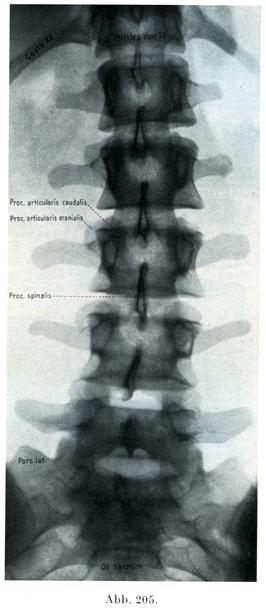

[図205]18 1/2才の少女の腰部脊柱レントゲン写真 腹背照射(6/11).